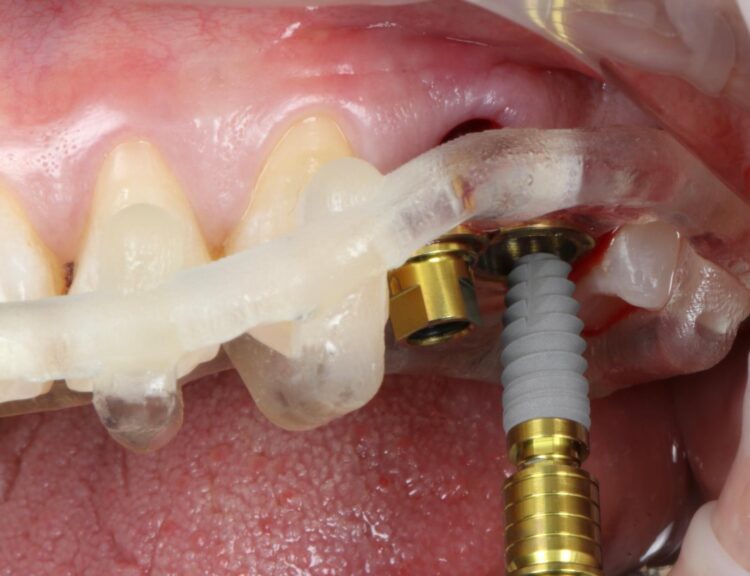

A CBCT and intraoral scans were taken and uploaded to the SMOP portal to design the surgical guide as per the clinical plan. These were 3D printed ahead of the surgical appointment.

The surgical guide was then placed in the mouth and the manufacturer’s specific drilling sequence followed, increasing the osteotomy in size incrementally.

The CONELOG® Progressive implant 3.8mm is my go-to for premolar sites. The implant is versatile in its clinical application, suitable for use in healed ridges and fresh sockets, providing good stability for delayed and immediate implant placement protocols. It’s an all-in-one implant for me and I love using it.

Two 3.8mm diameter CONELOG® Progressive-Line implants were placed through the guide, following the plan precisely. The UL4 implant was longer (11mm) to ensure sufficient apical bone was engaged for primary stability, it was also positioned in the palatal root to ensure good engagement with the bone and better bone to implant contact. A sizable jump gap was noted between the implant and the buccal plate of around 5-6mm. From a biological perspective, the jump gap can be left because the ridge would heal to leave a sufficient buccal plate. However, the literature[iv] shows that grafting reduces the amount of bone resorption post implant placement, which was one of the reasons that augmentation was indicated in this case.